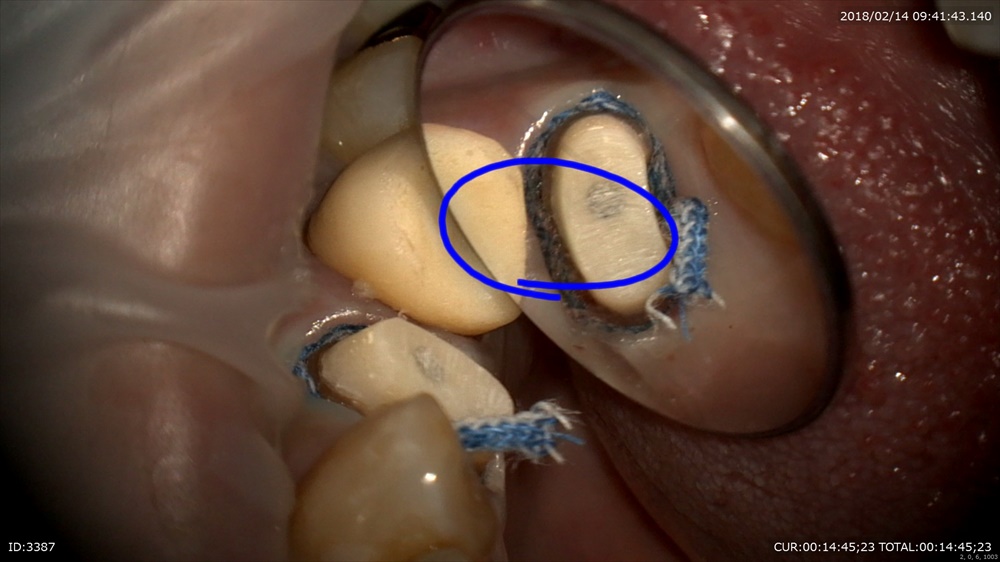

次の方は精密根管治療が終了しかぶせ物の型取り。

腫れも消えて嬉しい!!

型取り

写真を撮ってどれがかぶせ物かわからないようにオーダーメイドへ。セラミスト間中先生の出番。